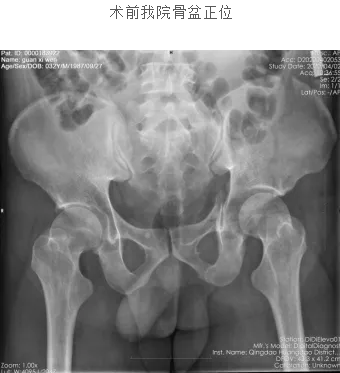

诊断:

1.骨盆骨折(左侧髂骨、耻骨上下支)

2.髋臼骨折(左侧)

3.多发腰椎骨折(L1椎弓根、L4椎体、L1、2左侧,L4、5双侧横突)

4.肋骨骨折(左11-12)

5.1型糖尿病

6.胸椎骨折(T11)

7.颅脑损伤

8.尿道损伤

9.电解质紊乱

10.中度贫血(失血性)

经过10天的综合调整,孙大夫着力控制血糖理想,病情平稳,一切本着“控制费用最低,钱花在刀刃上”的原则。王吉先主任主持术前讨论,统一思想:行骨盆、髋臼骨折治疗,行3块普通钛板复位固定骨折,力求达解剖复位。腰椎、、胸椎、肋骨骨折保守治疗。

在全身麻醉下行骨盆骨折切开复位钛板内固定、左侧髋臼骨折后路切开复位钛板内固定术

术后消肿、抗生素、预防血栓等药物诊疗。积极换药,刀口无感染。术后3日复查X片及CT,内固定合适,骨折复位良好。